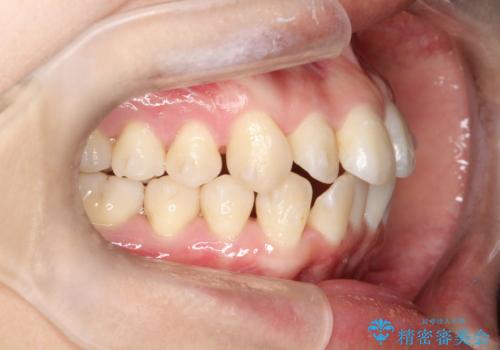

【インビザライン】前歯の凸凹をなおしたい

- 前歯の凸凹をなおしたいことを主訴にインビザラインにて矯正治療を行いました。

患者様にしっかりとインビザラインを使用して頂けたことで綺麗な仕上がりとなりました。